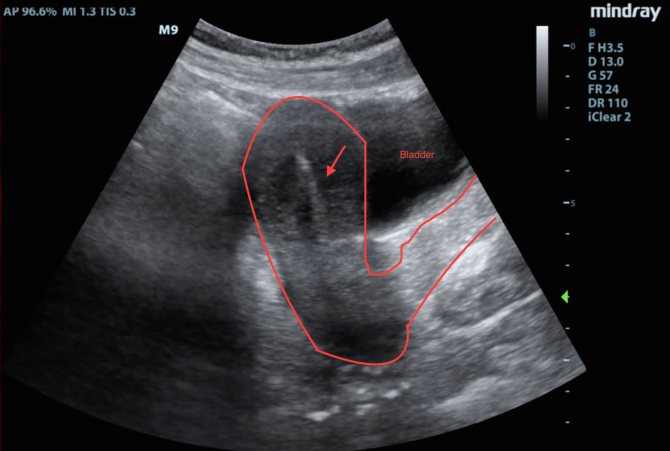

- пройти УЗИ малого таза.

Через 10 дней проводится плановый медицинский осмотр. При необходимости (для контроля местоположения спирали) назначается УЗИ. Если нет никаких осложнений и спираль установлена правильно, женщина возвращается к привычному для нее ритму жизни.

- Если боль возникла во время установки ВМС (чаще внезапная и сильная), то можно заподозрить перфорацию (прокол) матки. Это довольно редкое осложнение, но очень серьезное, из-за которого может потребоваться оперативное вмешательство. Для исключения такого грозного осложнения проводят УЗИ.